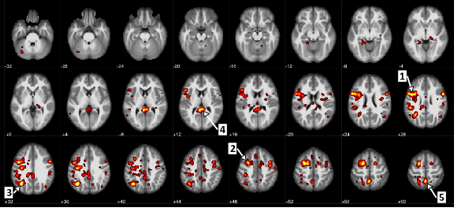

Ici, nous voyons les régions du cerveau qui montraient une différence statistiquement importante entre les patients atteints de schizophrénie et les patients qui ne le sont pas. Par exemple, la flèche 1 identifie la circonvolution frontale ascendante, ou le cortex moteur, et la flèche 5 indique le précuneus qui touche le traitement de l’information visuelle.